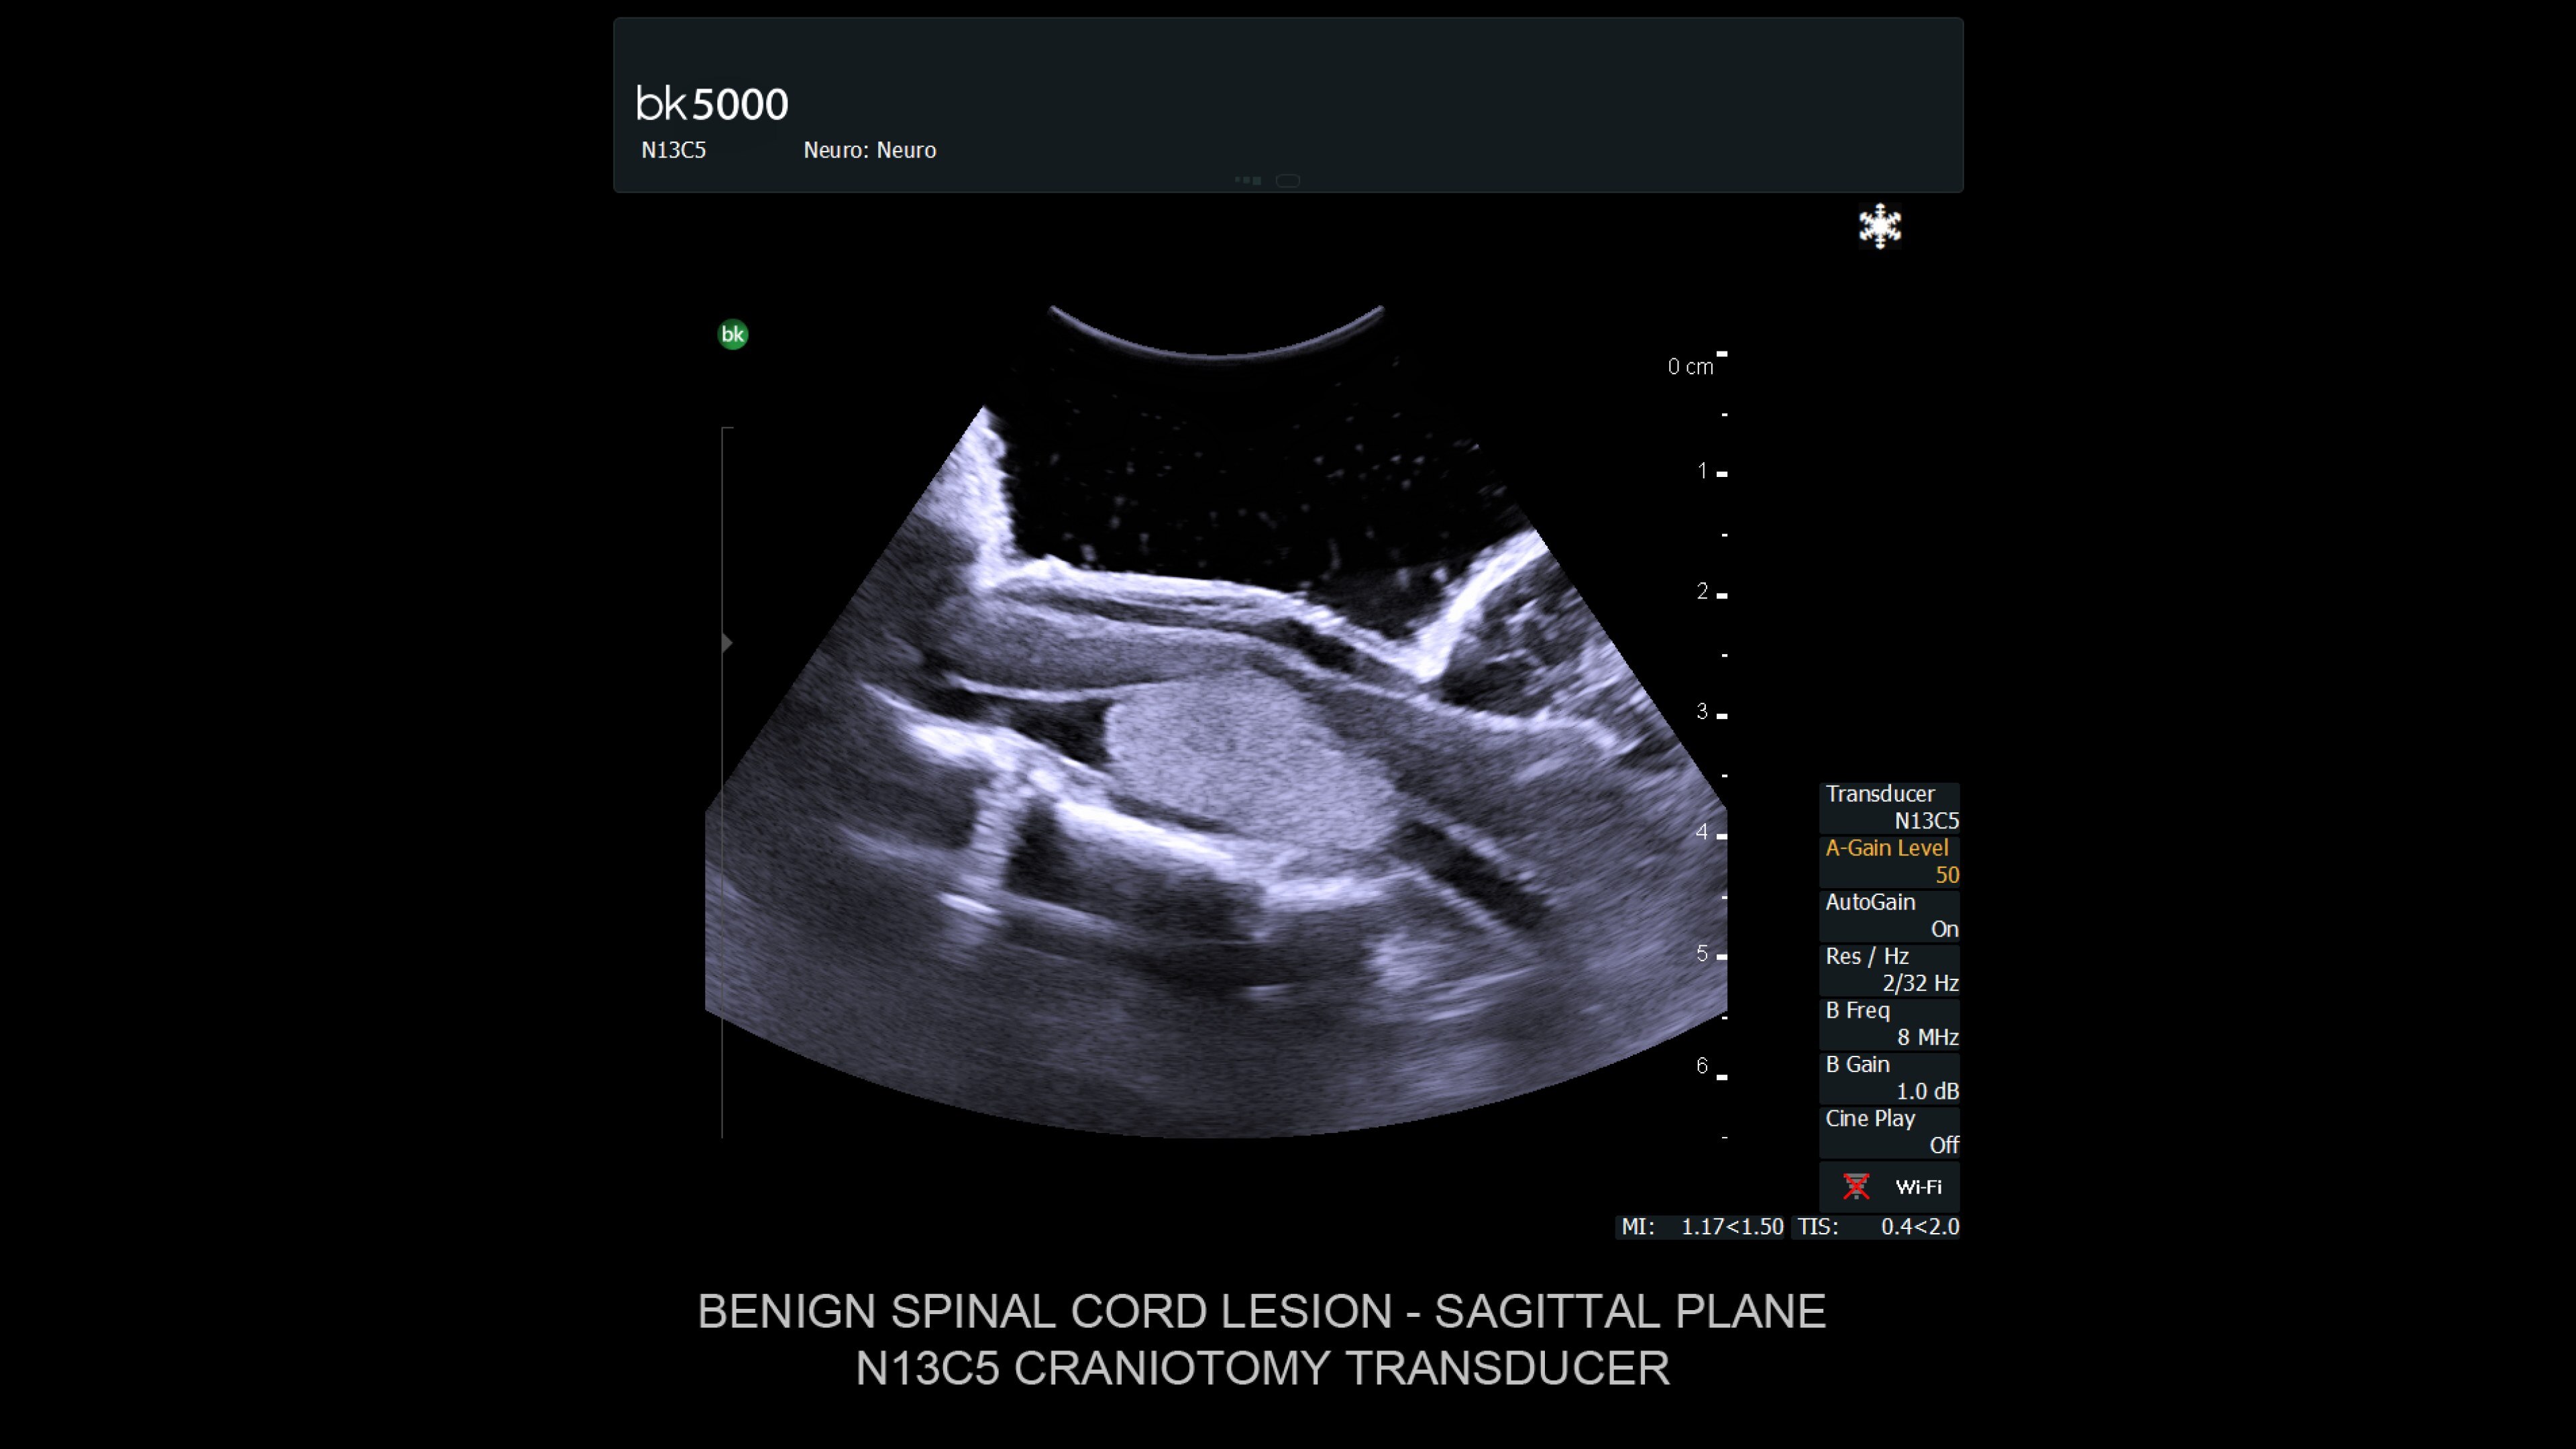

Ultrasound enhances neurosurgery by providing real-time navigation and lesion identification, crucial as preoperative CT/MRI data can be outdated. The bk5000 system offers high-quality images to see lesion margins and determine actions. Advanced graphics processing ensures immediate, auto-optimized images.

• Neurosurgery transducers: High-resolution, sterilizable transducers provide detailed brain and spinal cord images. The Smart™ button allows easy activation, freezing, storing, or printing of images. Disposable needle guides aid lesion targeting.